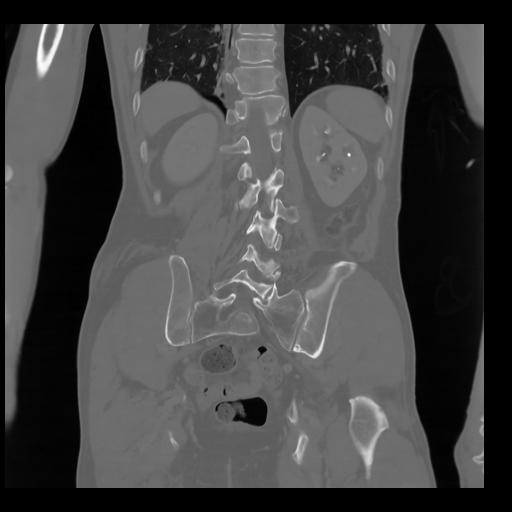

35 CUERPO,CE,Coronal,3.000,CUERPO,Coronal,